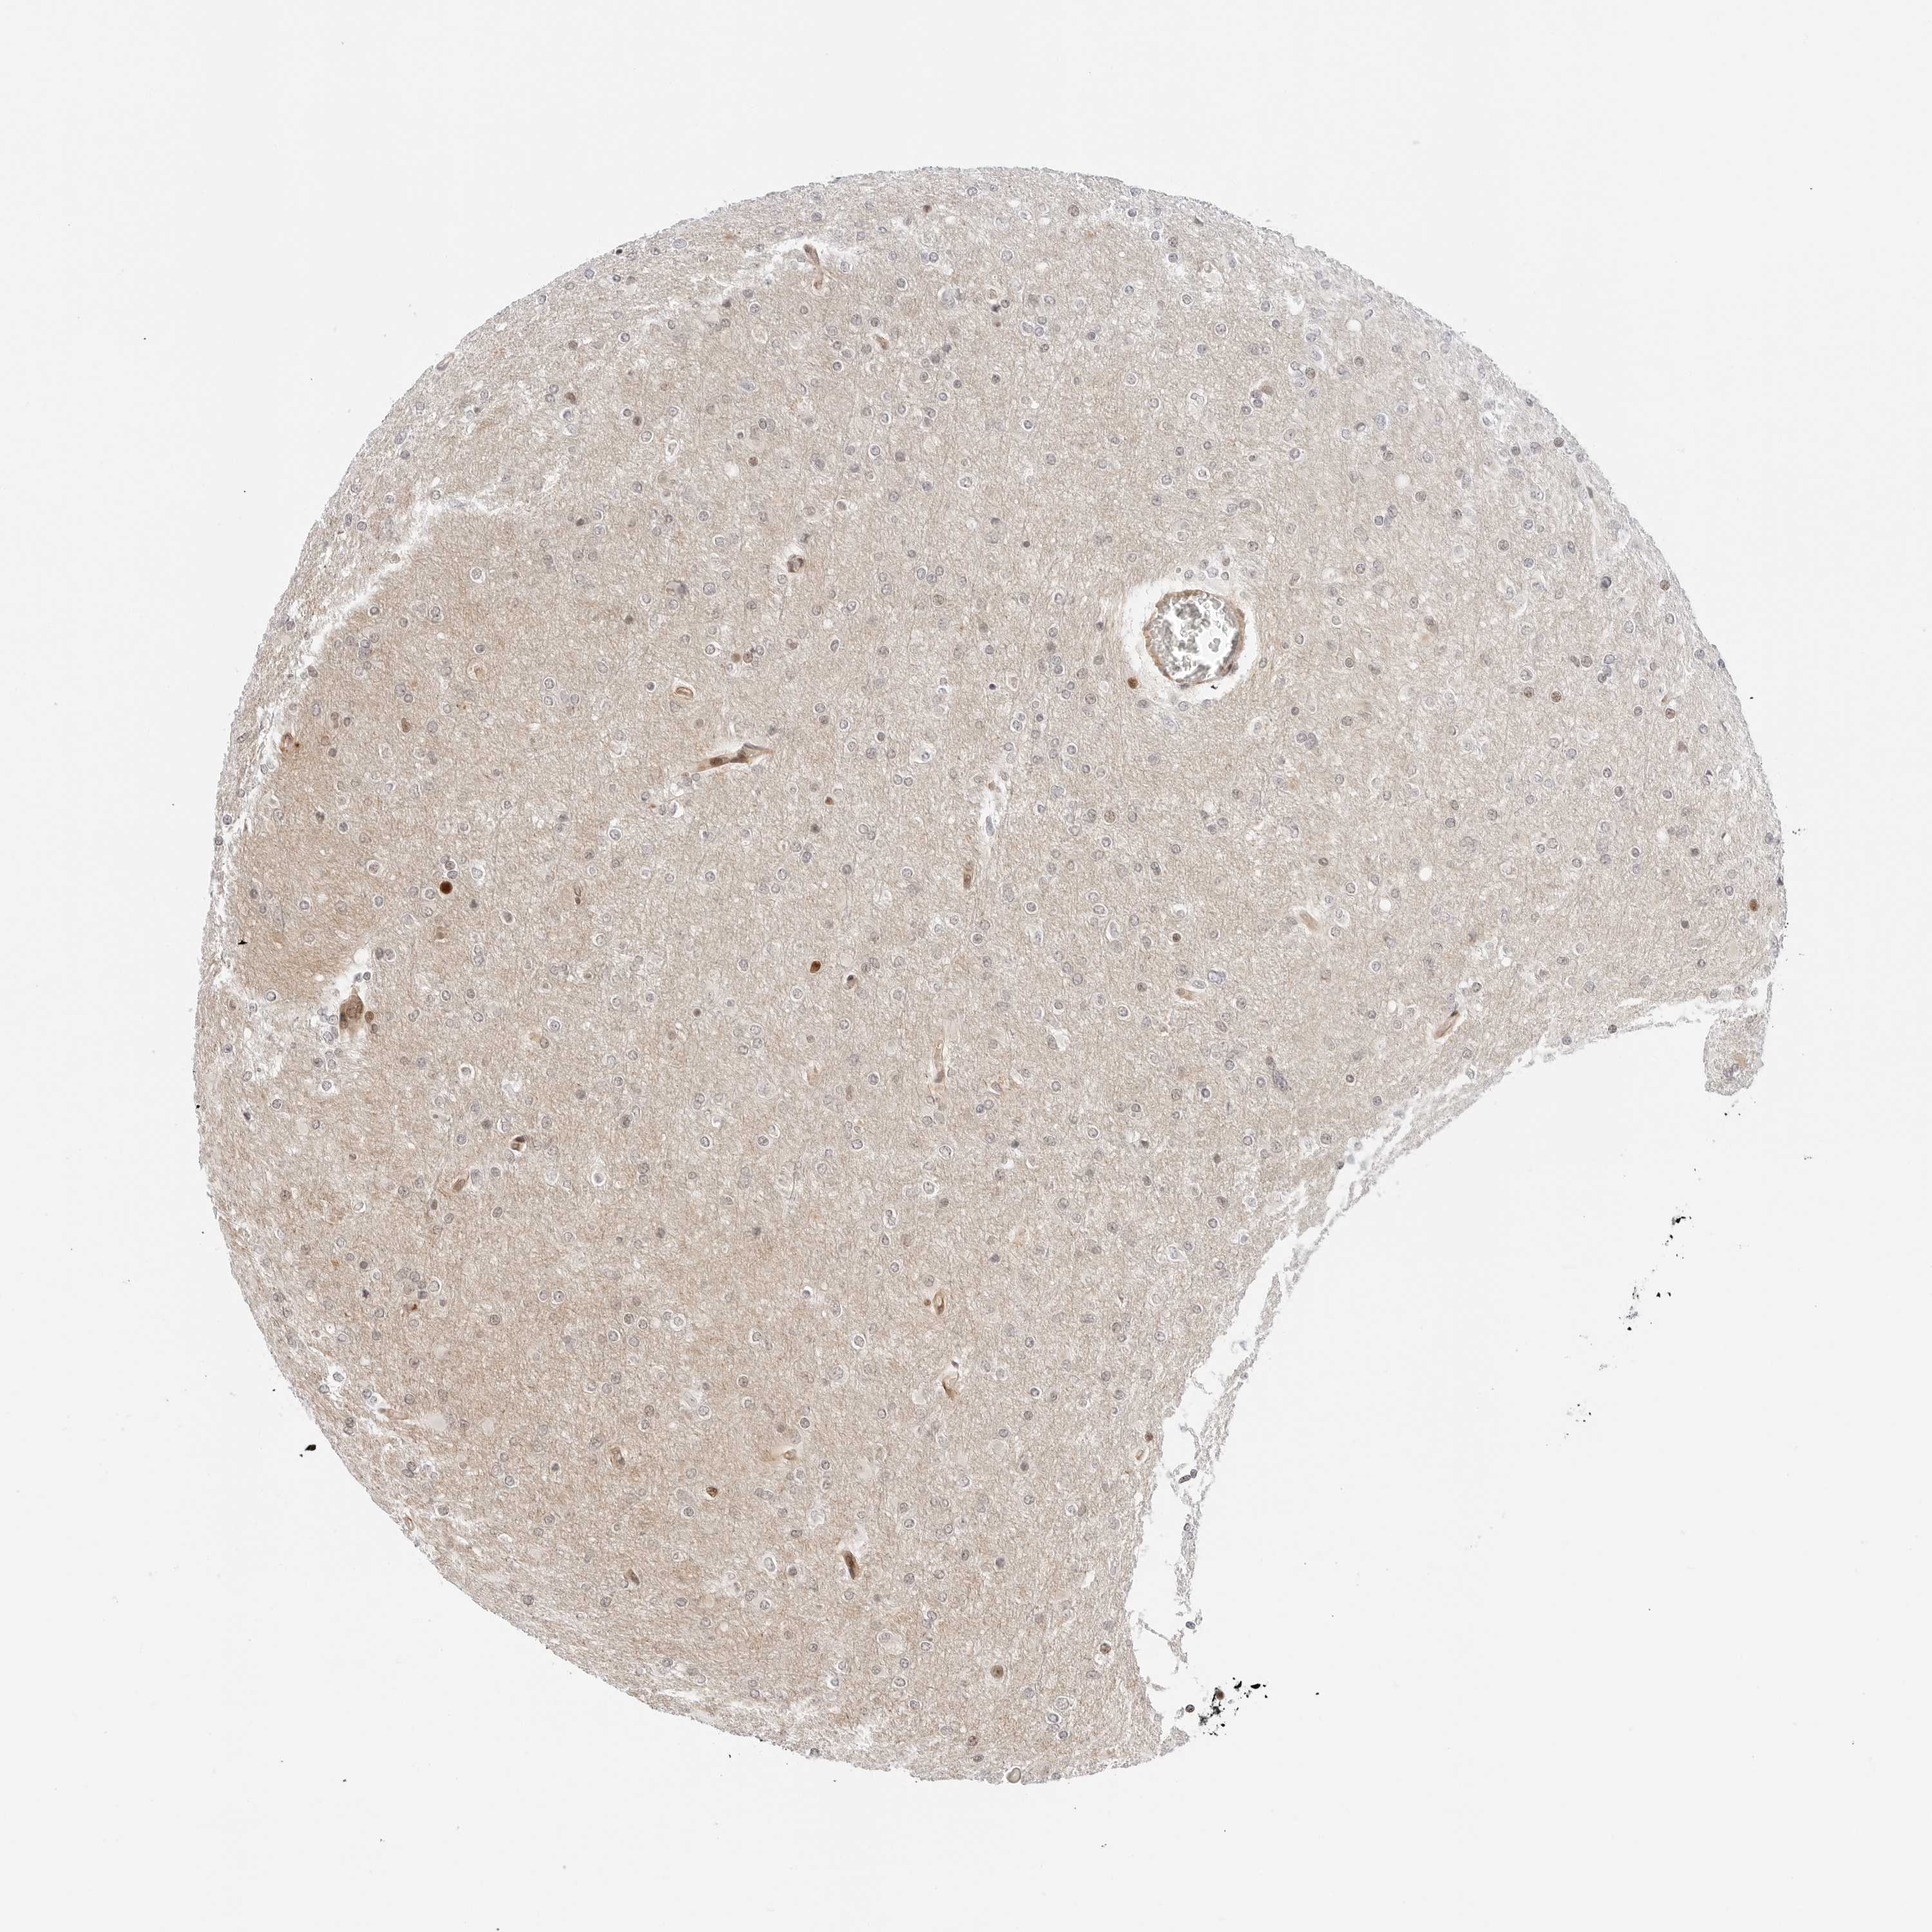

GLIOMA - Protein expressioni

A mouse-over function shows sample information and annotation data. Click on an image to view it in a full screen mode. Samples can be filtered based on level of antibody staining by selecting one or several of the following categories: high, medium, low and not detected. The assay and annotation is described here.

Note that samples used for immunohistochemistry by the Human Protein Atlas do not correspond to samples in the TCGA dataset.

Antibody stainingi

Antibody staining in the annotated cell types in the current human tissue is reported as not detected, low, medium, or high, based on conventional immunohistochemistry profiling in selected tissues. This score is based on the combination of the staining intensity and fraction of stained cells.

Each image is clickable and will lead to virtual microscopy that enables deeper exploration of all samples and also displays staining intensity scores, fraction scores and subcellular localization as well as patient and tissue information for each sample.

Antibody HPA026833

Staining

High

Medium

Low

Not detected

Intensity

Strong

Moderate

Weak

Negative

Quantity

>75%

75%-25%

<25%

None

Location

Nuclear

Cytoplasmic/membranous

Cytoplasmic/membranous,nuclear

Glioma, malignant, High grade

Glioma, malignant, Low grade

Glioblastoma, NOS